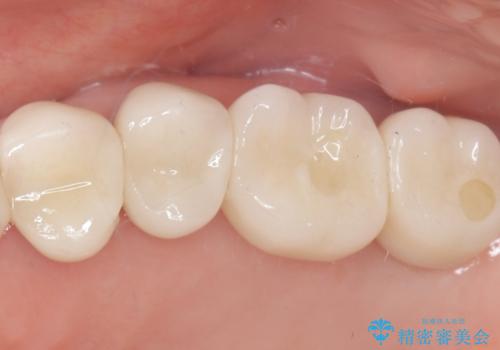

今回のケースでは、特に難しいとされる奥歯の抜歯即時インプラントを適用しました。まず、炎症を起こしていた左上6番と7番を慎重に抜歯し、その直後にインプラントを埋入。この抜歯即時埋入により、歯を失ってからインプラントを埋入するまでの期間を省くことができ、骨の吸収を最小限に抑えられました。痛みや腫れもほとんどなく、患者様は「思ったより楽だった」と仰っていました。結果的に、通常であれば1年近く要する治療をわずか3ヶ月で完了。機能性と審美性を兼ね備えた新しい奥歯により、快適な食生活と笑顔を取り戻していただけました。